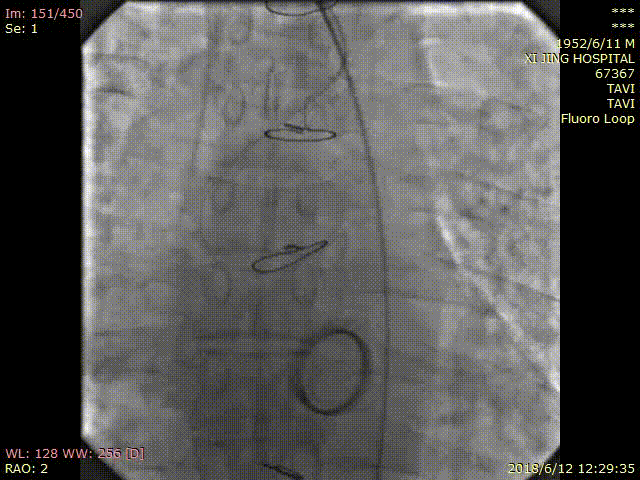

术中DSA影像:

TAVR术后造影无瓣周漏